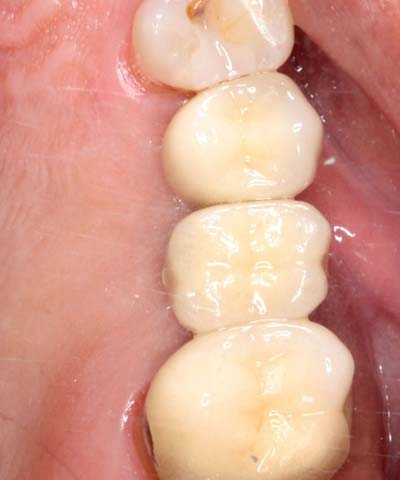

鼻竇增高術(側窗) 首頁 案例分享 人工植牙 鼻竇增高術(側窗) 鼻竇增高術(側窗) 製作多年的牙橋,牙根斷裂,發炎 鼻竇增高術 側面開窗 抬高鼻竇 鼻竇增高術 置入骨粉 覆蓋再生膜,保護骨粉 術後追蹤,傷口良好 裝戴正式假牙 完成 8年追蹤 左上牙根斷裂 植牙重建 九年追蹤